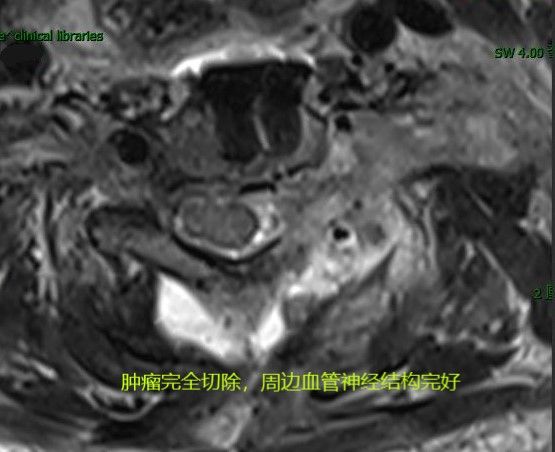

经后路切除椎管及椎间孔肿瘤,给肿瘤“除根”,为脊髓“减负”。

经颈前路切除残余肿瘤,臂丛神经保护完好。